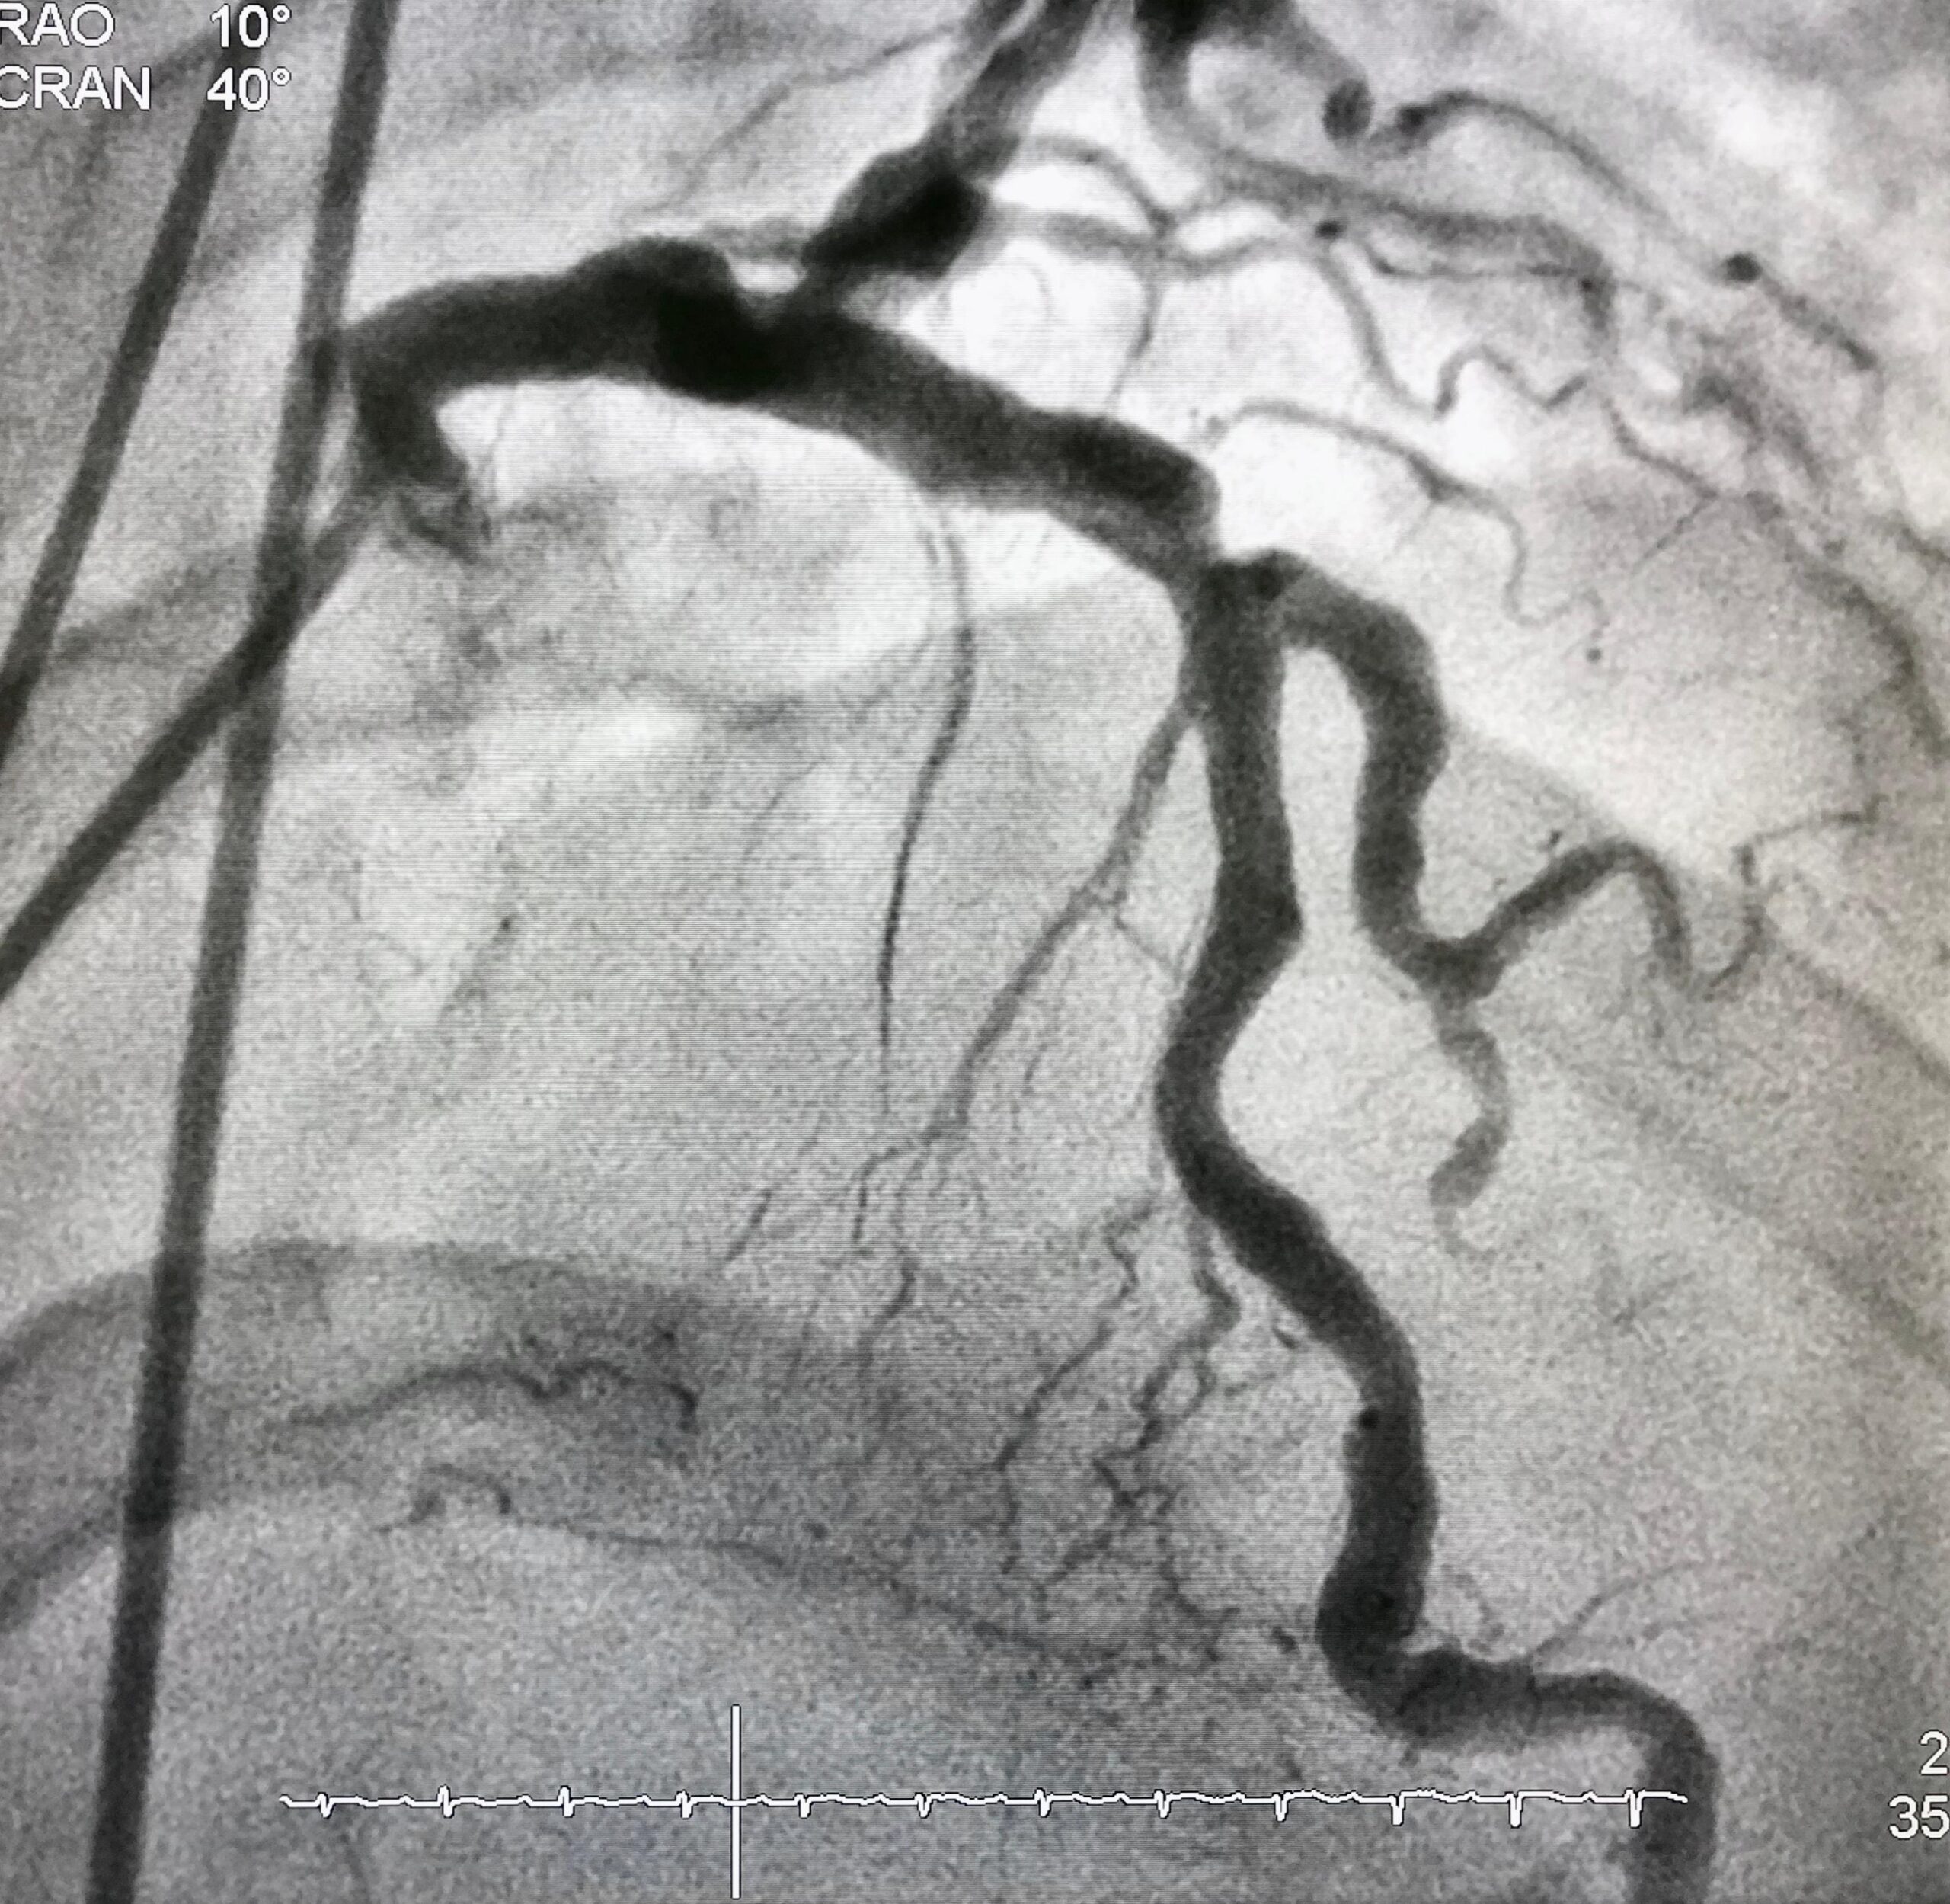

Ez lehet úgynevezett konzervatív terápia: gyógyszerek alkalmazása, életmódbeli változtatások, esetleg fizikoterápia, vagy valamilyen, a vérkeringést azonnal javító beavatkozás: műtét, katéteres értágítás/megnyitás. Azt, hogy melyik megoldás választandó, a vizsgálatok eredménye alapján dönthetjük el. Az első fázis, az ambuláns fizikális és eszközös diagnosztika, Doppler, Color Duplex Ultrahang, áramlási sebesség-, szöveti oxigenizáció mérés után bonyolultabb képalkotó eljárások pl. katéteres érfestés, CT esetleg MR is szükségessé válhatnak a megfelelő döntés meghozatalához. Ezek a vizsgálatok azonban Magyarországon az állami egészségügyben érhetőek el TB finanszírozottan, mint ahogy a műtéti és katéteres beavatkozások is itt és ilyen módon történnek. Ebben a fázisban a magyar állampolgároknak a betegirányításban tudunk segítséget nyújtani. A külföldi állampolgárok számára ezek fizetős jellegűek. Érsebész kollégáink a számukra biztosított hivatalos úton, közvetlenül tudnak segítséget nyújtani a megfelelő ellátó intézetben.